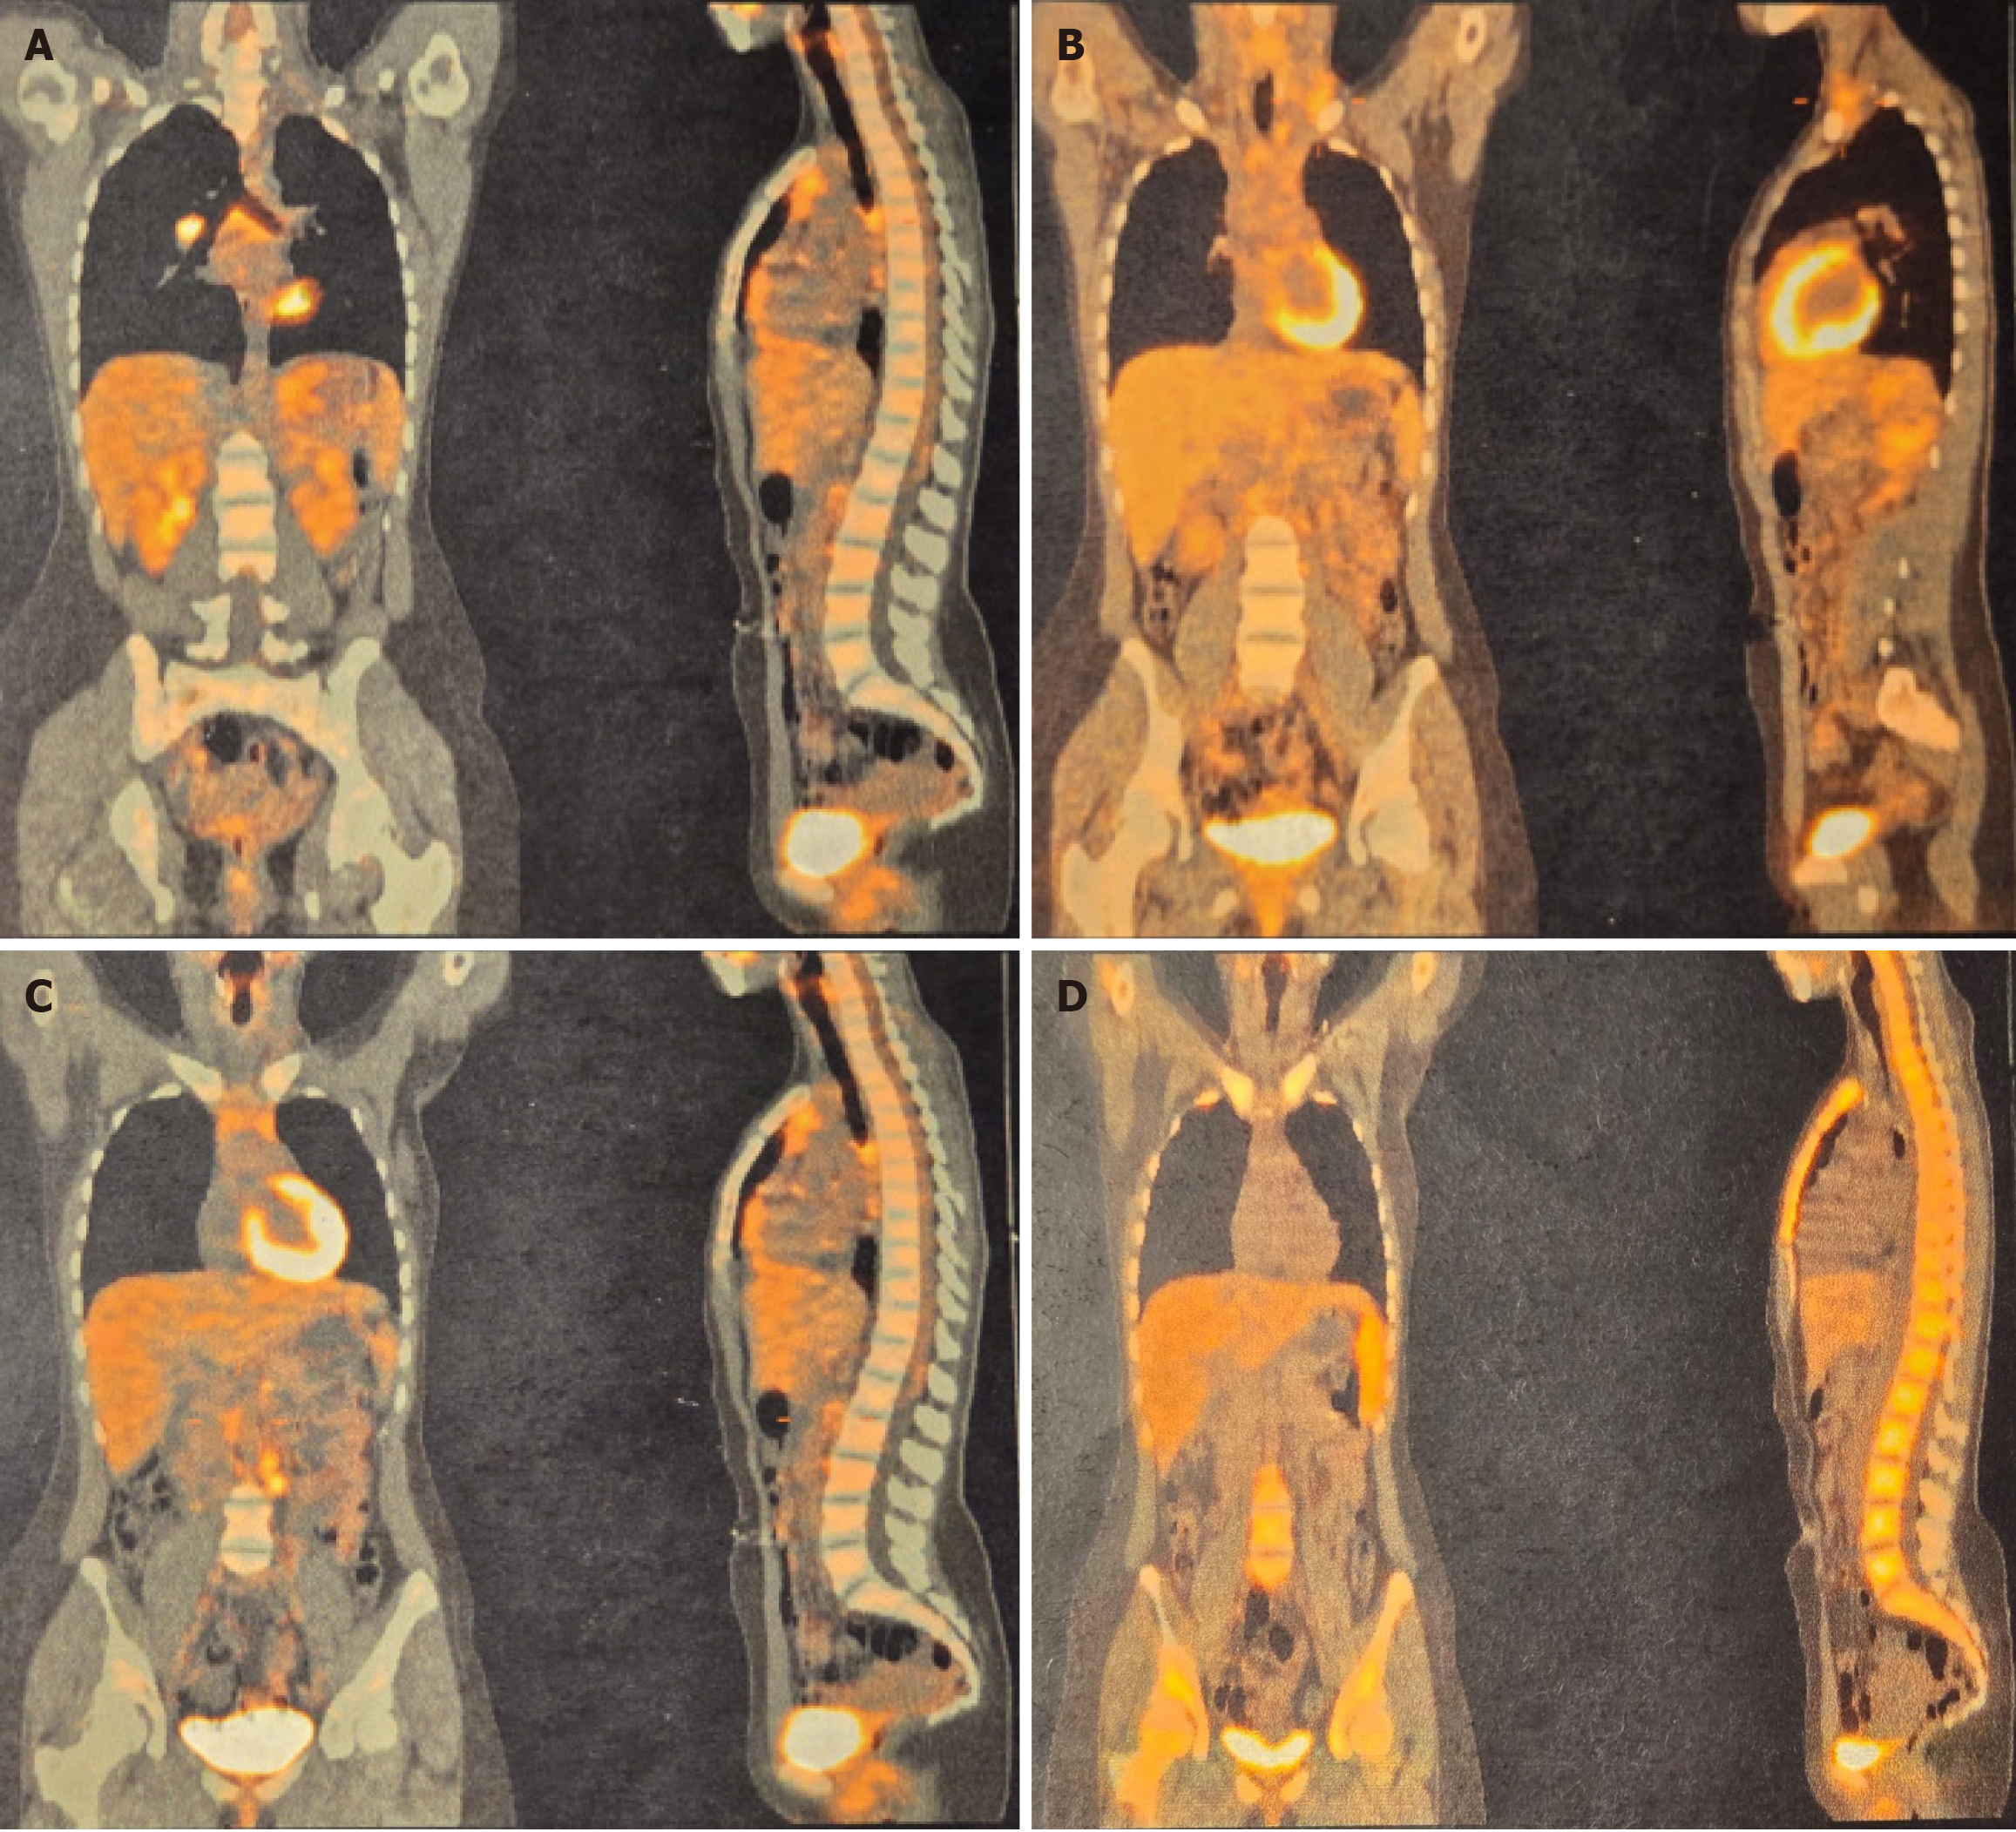

Figure 1 Patient A’s initial positron emission tomography-computed tomography scan.

A-C: Demonstrating increased fluorodeoxyglucose accumulation in the carinal, pulmonary hilar, left interaortocaval, and para-aortic lymph nodes. Increased metabolic activity is also evident in the left supraclavicular region, corresponding to the site of lymph node excision; D: After the first three cycles of doxorubicin, bleomycin, vinblastine, and dacarbazine chemotherapy, showing no evidence of pathological metabolic activity. Diffuse, reactive osteomedullary fluorodeoxyglucose uptake is present.